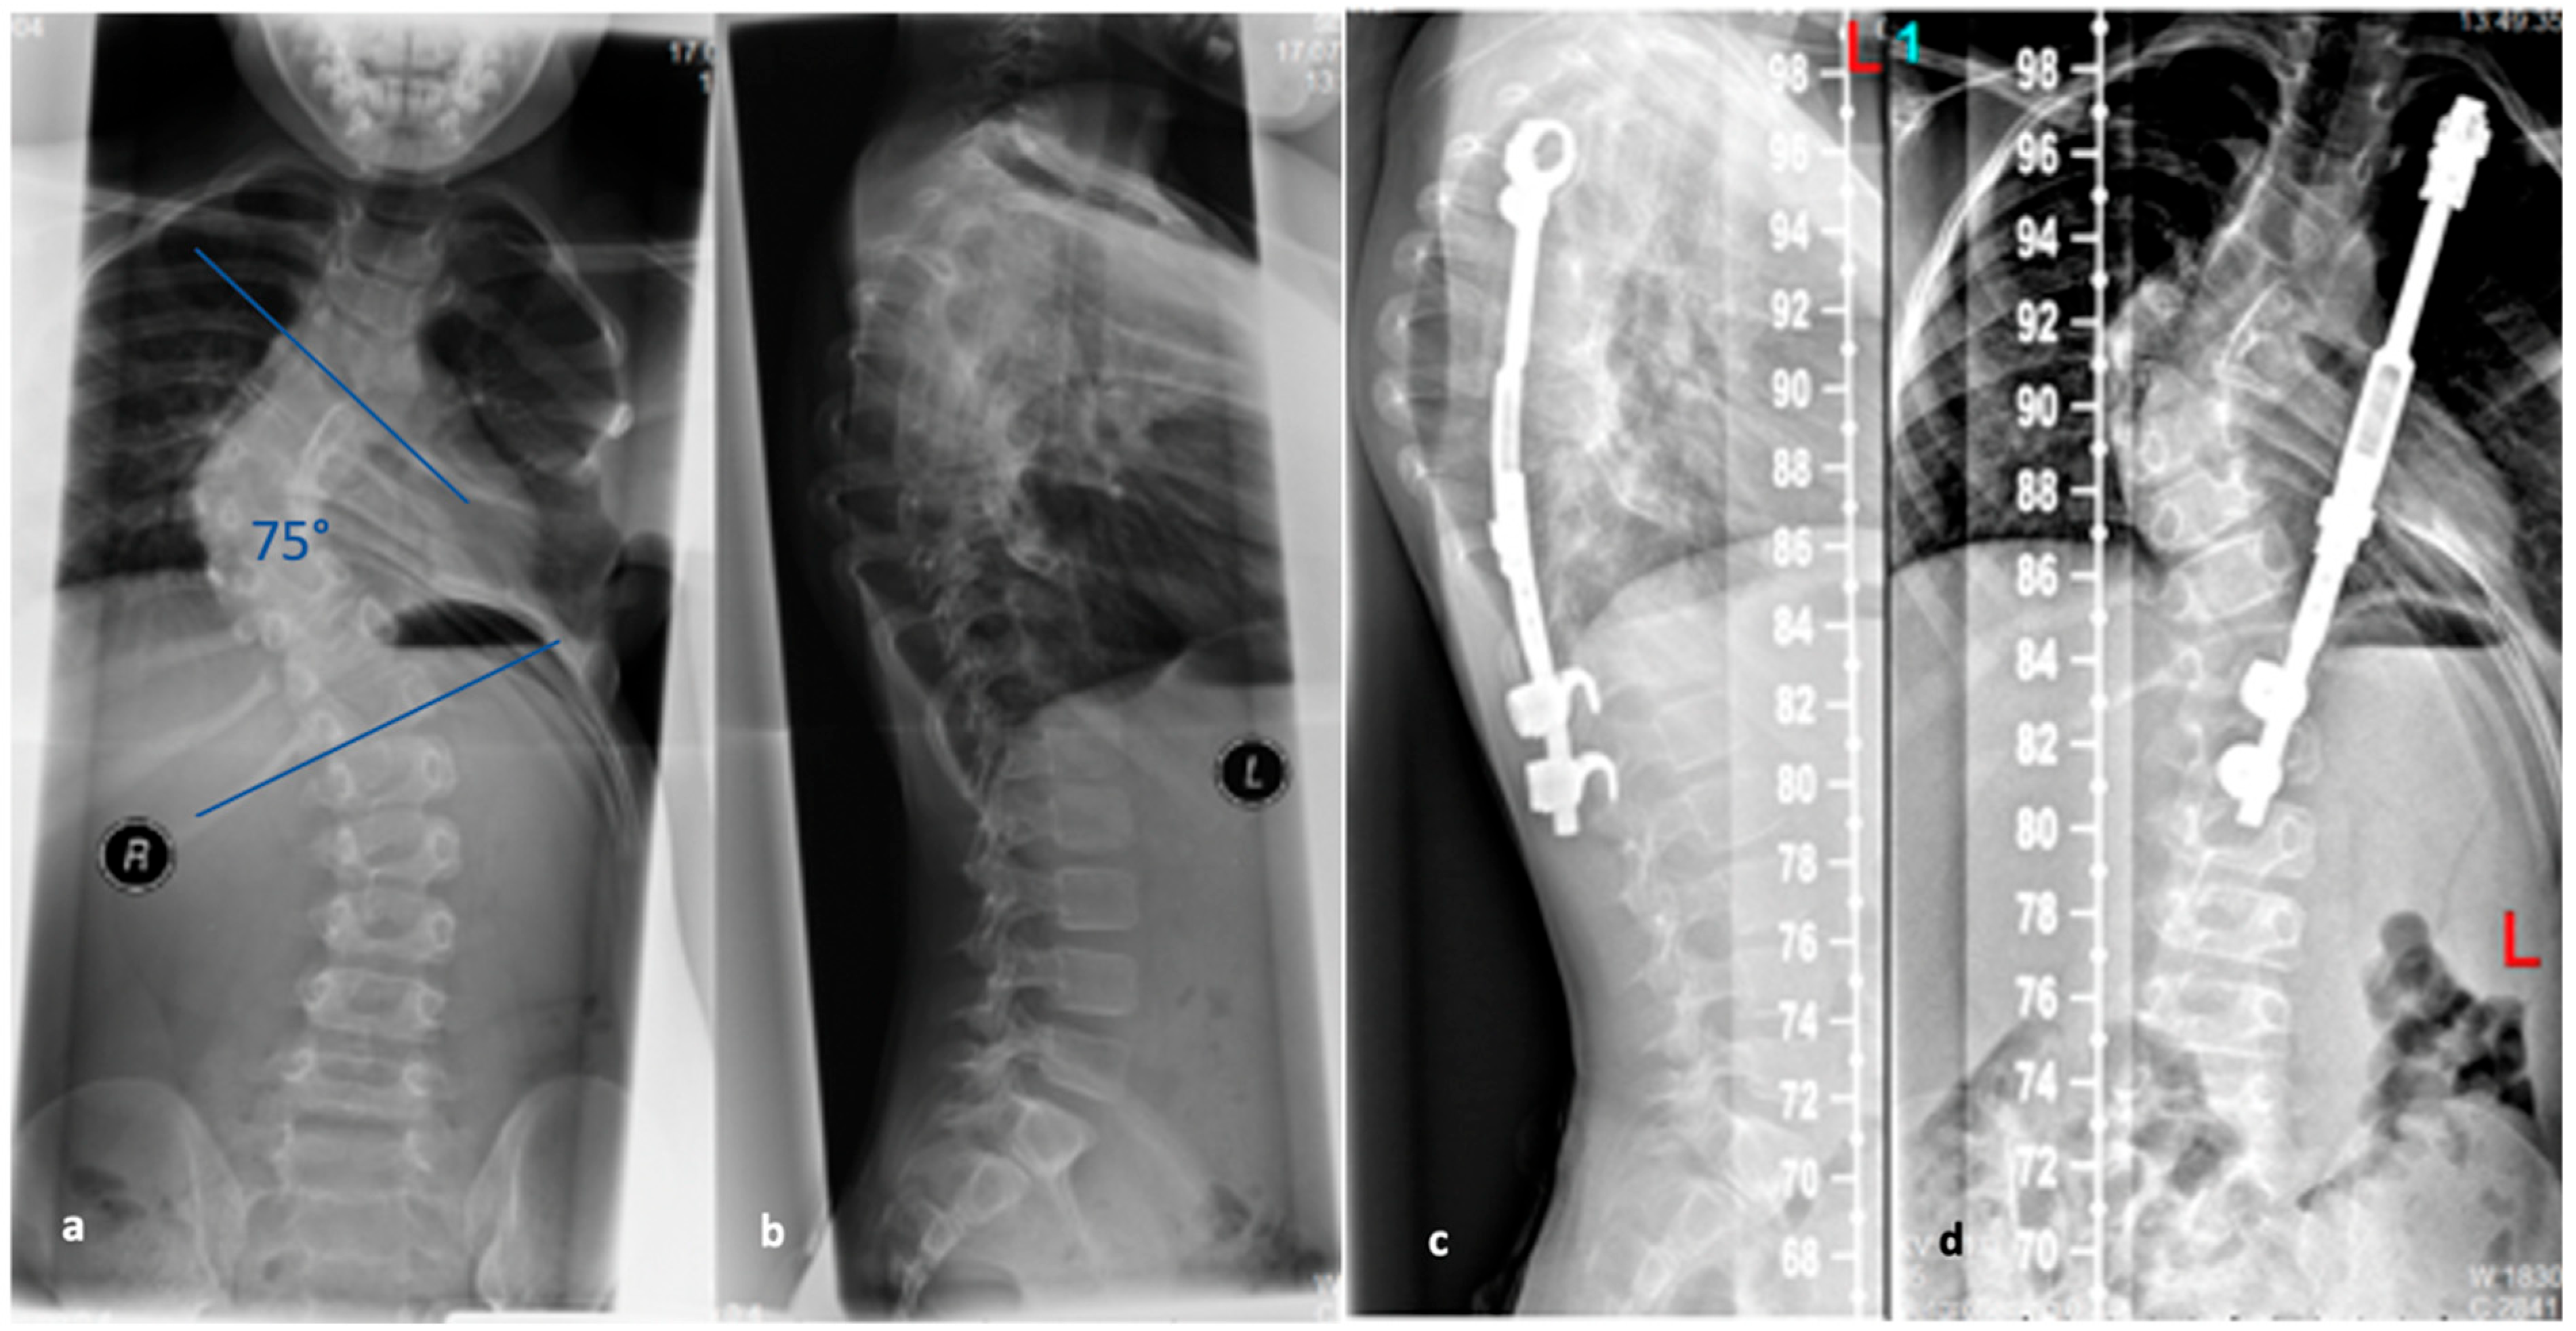

Several surgical techniques have been proposed to address SD, all of which involve three key steps: release of spinal structures, correction of the kyphosis (aiming for at least 50% correction), and spondylodesis with instrumentation [96]; see Figure 11. Some techniques include an anterior release to facilitate posterior curve correction, but the potential benefits of this approach remain uncertain, and it may lead to a higher occurrence of unfavorable effects such as higher complications rates, blood loss and operation time [98,99,100]. Earlier studies have shown favorable outcomes in terms of pain relief and spinal deformity correction following surgical intervention for SD with the most common complications reported being neurological (such as paraplegia), infectious, and respiratory in nature [93,95]. For rigid curvatures, anterior release followed by dorsal instrumentation and spondylodesis was the method of choice until about 20 years ago. However, in several studies, dorsal instrumentation with osteotomies and shortening of the dorsal column achieved comparable results to anterior–posterior procedures [101,102]. Lee et al. evaluated 17 studies and a total of 1147 patients in a meta-analysis. Here, the correction of the kyphotic malalignment between dorsal instrumentation with osteotomies and anterior–posterior spondylodesis was comparable [103]. Despite this, anterior release, fusion and posterior spinal fusion experienced significantly more complications than the posterior spinal fusion alone [101]. Therefore, it is not recommended to subject the patient to additional surgery (i.e., anterior release and fusion). A single posterior approach is adequate to achieve sagittal correction with a balanced spine and fewer associated complications.

4.4.1. Selection of the Instrumentation Range

The determination of the instrumentation range is certainly dependent on the chosen surgical procedure. The upper instrumented vertebra (UIV) is usually the proximal vertebra that still belongs to the curvature [104]. The selection of the lowest instrumented vertebra (LIV) can be the first lordotic vertebra (FLV) or the sagittal stable vertebra (SSV) according to Cho et al. [105]; see Figure 12. However, in the meta-analysis by Gong et al., instrumentation of the SSV proved to be superior to the FLV [106]. In this meta-analysis, the incidence of distal junctional kyphosis (DJK) in SD was reported to be 20.8%, and of these cases, 27.8% of patients had to be revised; 5.9% of the SSV cohort and 43.6% of the FLV cohort developed DJK [106].